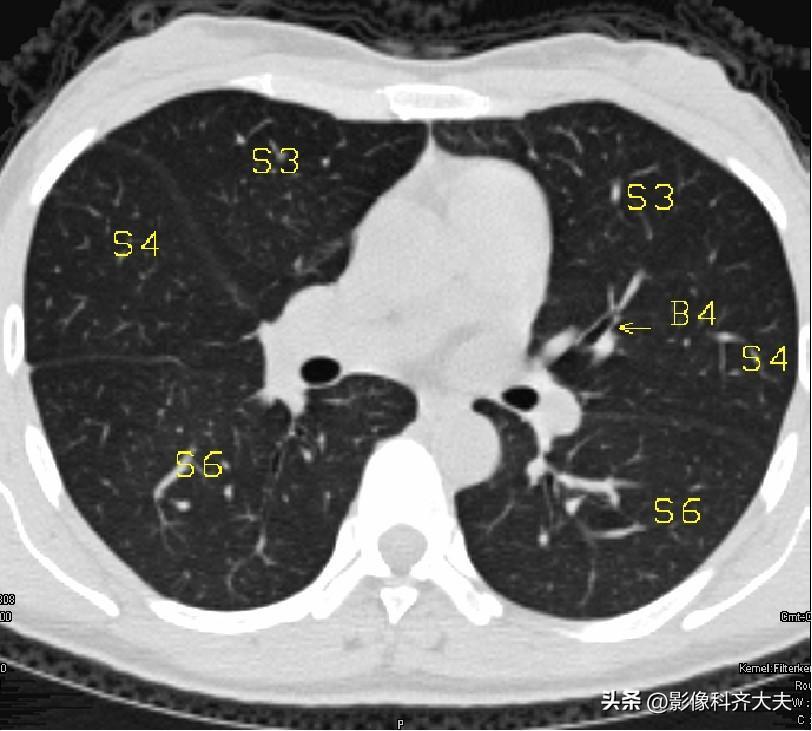

▲S4:右中叶外段/左舌上段

图11-隆突下3cm层面

▲B4:右中叶外侧段/左舌上段支气管